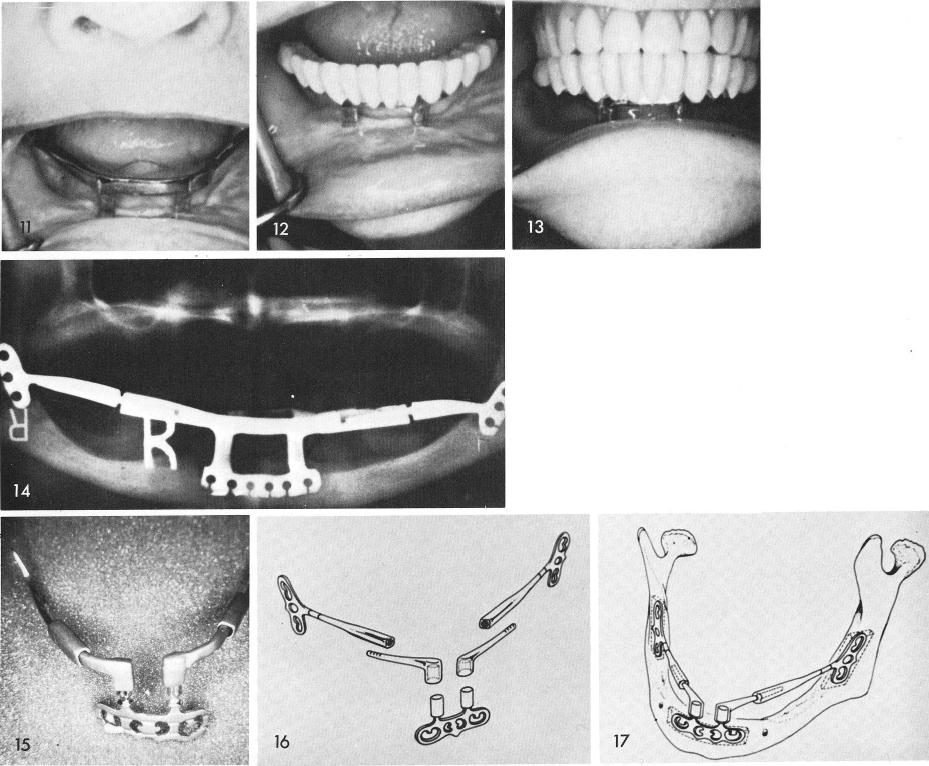

poor implant design in the posterior areas, figs. 9, 10. Fig. 11 shows excellent healing. The all acrylic splint is cemented over the implant with Duralay acrylic cement, figs. 12, 13. A great deal of space was originally left beneath the prosthesis and soft tissues so the appliance would act as a sanitary bridge. The post-operative x-ray, fig. 14.

An early five piece symphyseal-rami-system developed by the author, fig. 15. A later version of the system, figs. 16, 17.

1 Acrylic splint fixed on mandibular implant with Duralay acrylic cement